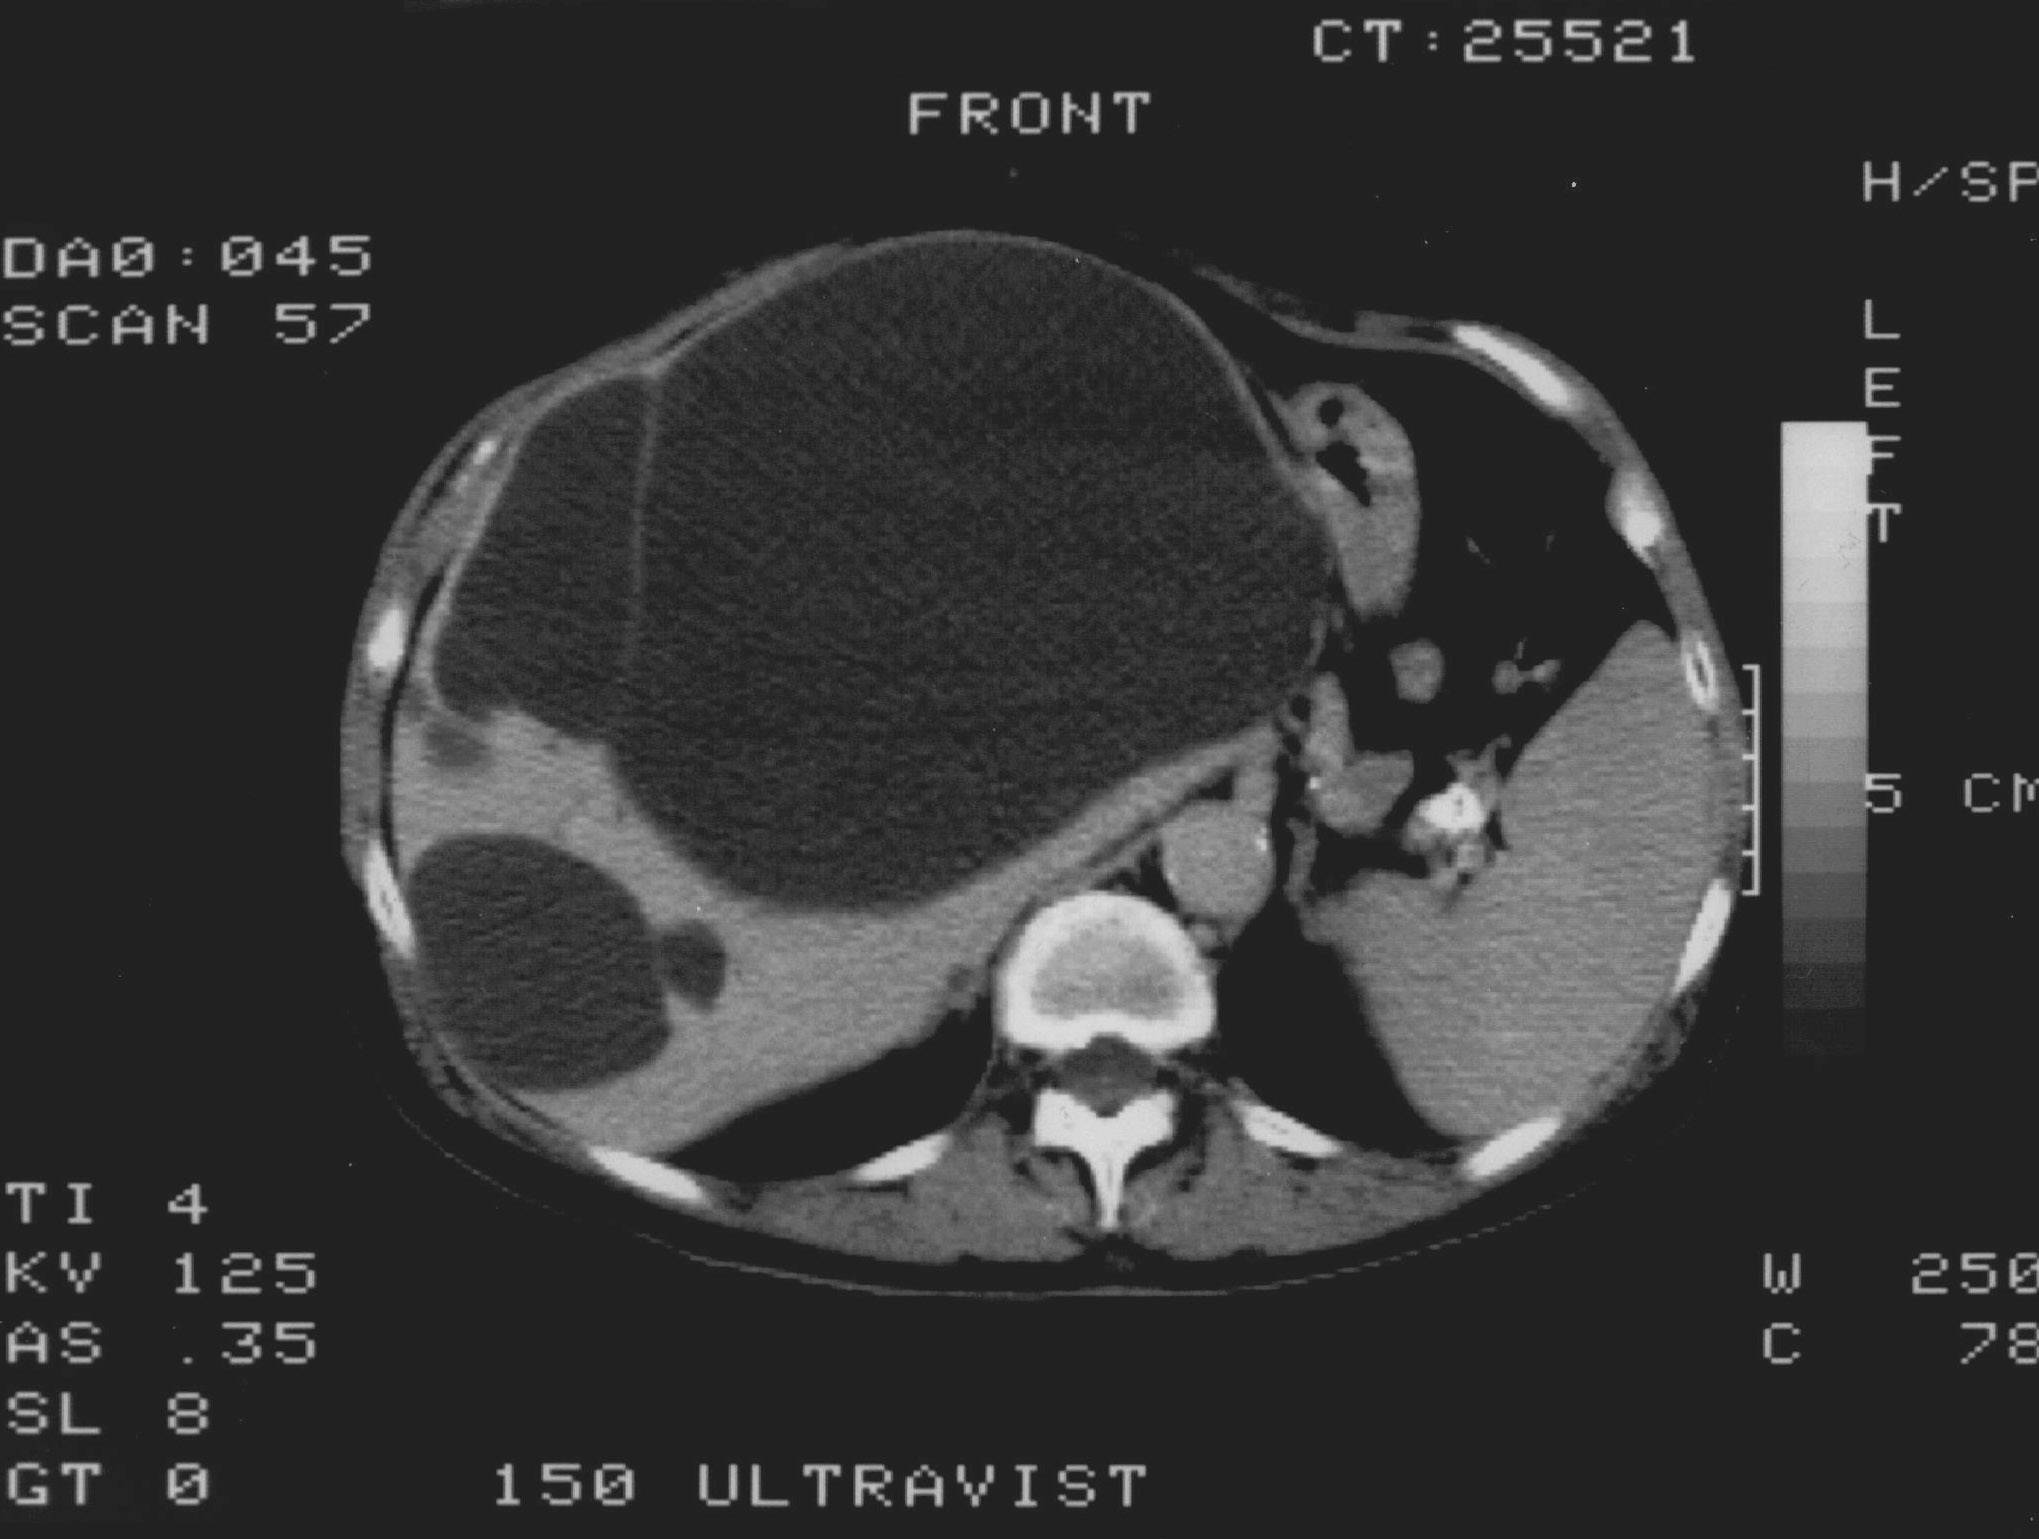

19.2.2.2. CT guided biopsy

Ideal method if the lesion is located either in the chest (figure 5.), mediastinum, retroperitoneum (figure 6.) or the pelvis.

Image

Figure 6. – CT guided pancreatic biopsy